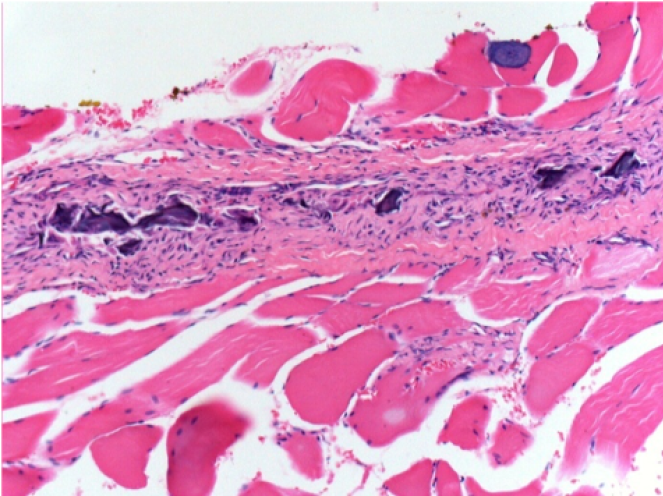

3 mesi dopo Iniezione di Endopeel

Scatola Nr 4

3 mesi (Giorno90) dopo iniezione 0.1ml di Endopeel nel muscolo pretibiale destro ( Dx)

Sx : Controllo-100x-Giorno90

Dx:100x-Giorno90